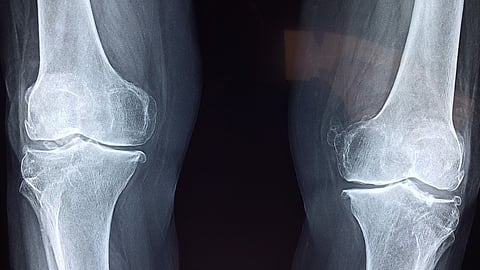

Each month, the department performs approximately 60 knee replacements, 20 hip replacements, and eight complex spinal surgeries for scoliosis each spinal procedure lasting up to 10 hours.

Dr. Nagesh noted that NIMS’s affordable pricing attracts patients from across the region. For example, scoliosis surgeries that cost ₹8 to ₹10 lakh at corporate hospitals are available for about ₹1 lakh at NIMS. Knee replacements, typically priced at ₹3-5 lakh in private hospitals, are conducted for under ₹1.5 lakh.

Impressive Figures Each year, NIMS orthopedic surgeons perform nearly 5,000 surgeries, many requiring complex, multidisciplinary approaches. Joint replacements account for approximately 800 cases annually, spinal surgeries for 85, and orthopedic oncology cases for around 400. The team also performs 300 arthroscopy procedures, 25 endoprosthesis surgeries, and provides 100 artificial limbs annually, Dr. Nagesh added.